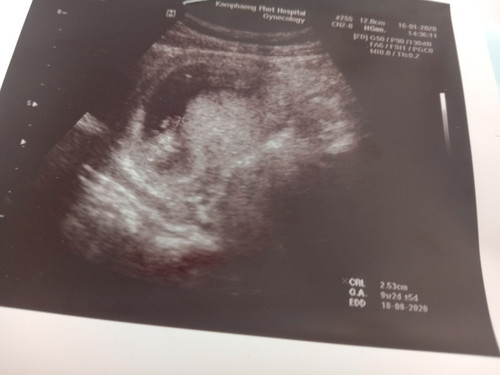

2เดือนกว่าๆเเล้ว ลูกตัวเล็กไปไหม

ไม่ค่ะ ดูเลขตรง G.A. ได้ค่ะ ก็สอดคล้องกับอายุครรภ์ดี